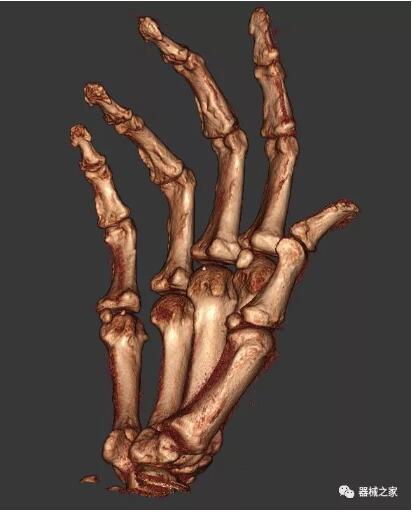

以下是這些“特立獨(dú)行”的CT所拍出來的圖像: